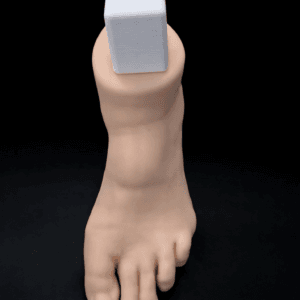

| Pathology | Pes Cavus |

| Procedure | Cole Osteotomy, Dwyer, Lateralizing Calcaneal Osteotomy, Metatarsal Dorsiflexion Osteotomy |

| Area | Midfoot |

| Modularity | Single-piece |

| Material | Opaque |

Pes Cavus – Bone Model